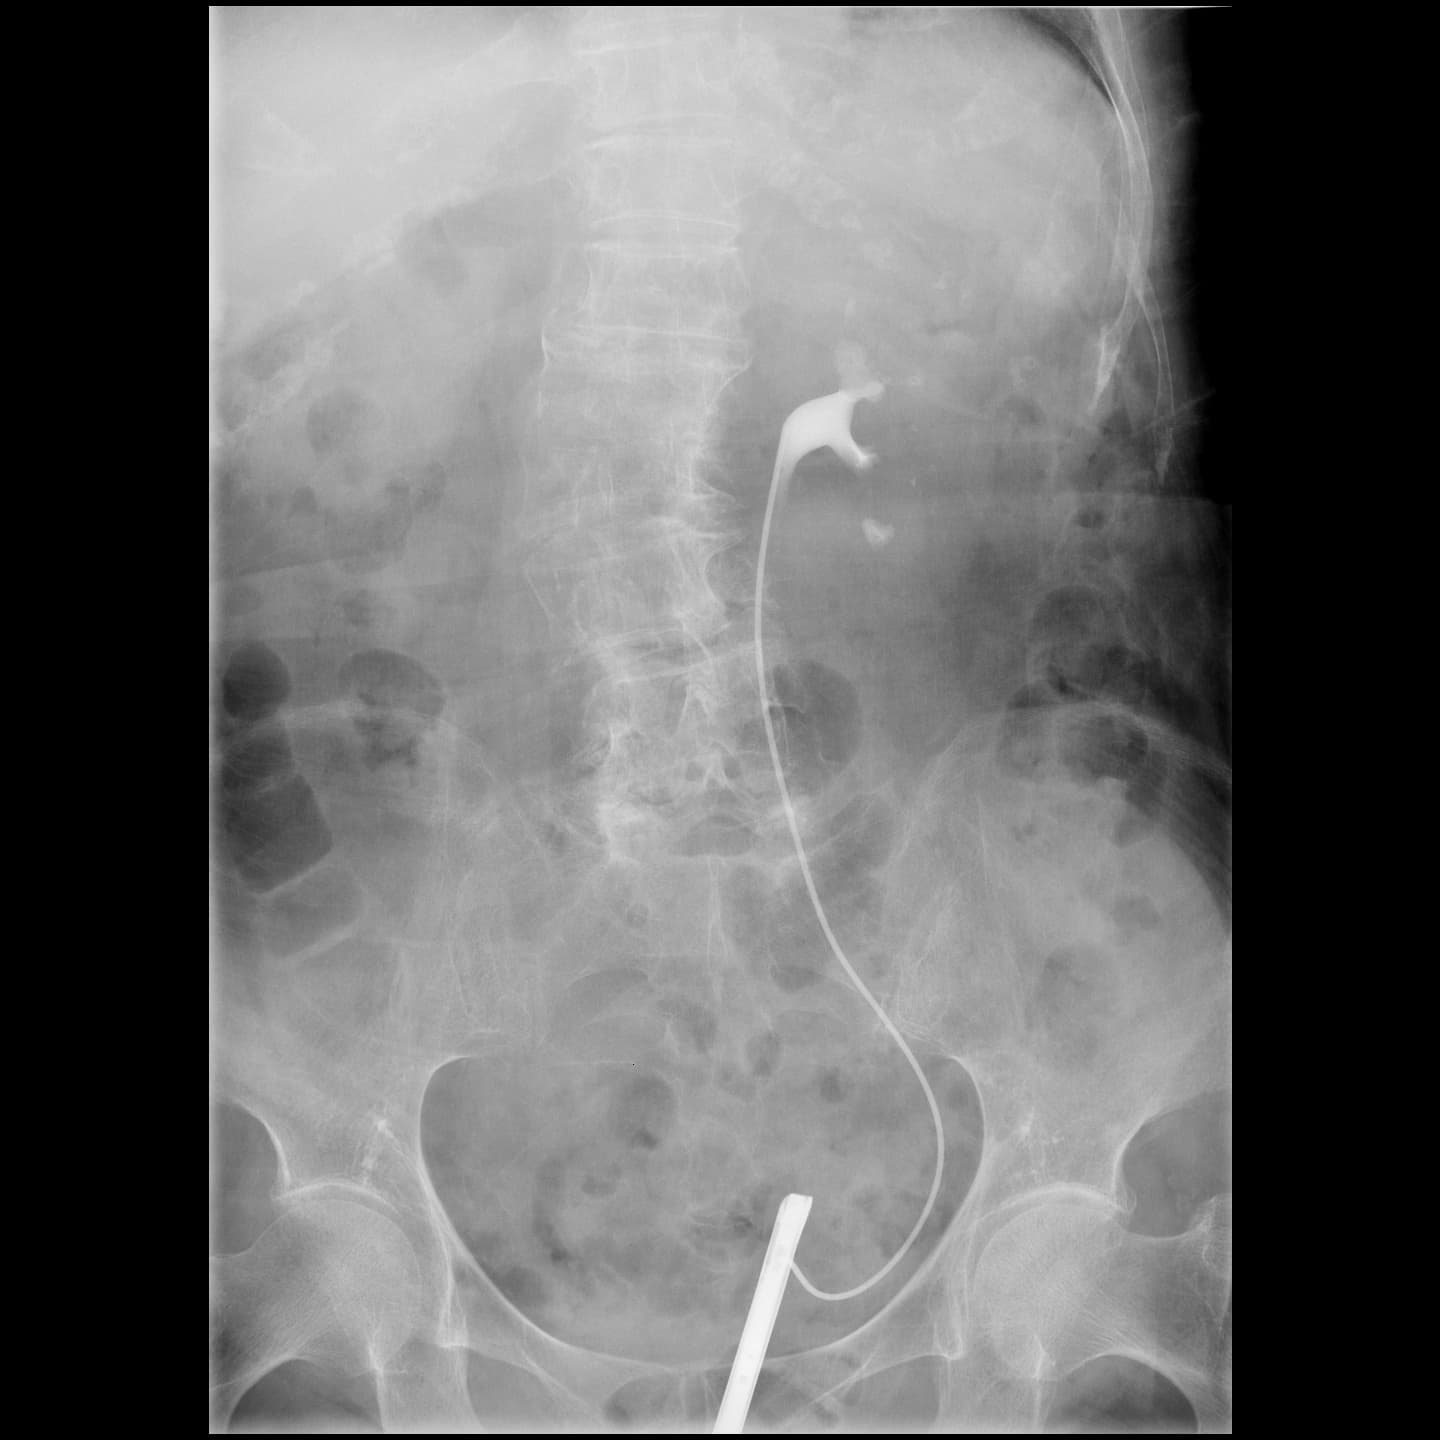

泌尿器部門に特化した装置です。腎臓や尿路、膀胱の機能や形態を調べるため、尿路造影検査を行っています。

主な検査として、X線透視下で尿管カテーテルの挿入を行っています。

尿管皮膚婁、腎瘻・膀胱瘻増設などの治療も行います。また、小児に起こりやすい膀胱尿管逆流症に対して、排尿時膀胱尿道撮影なども行っています。